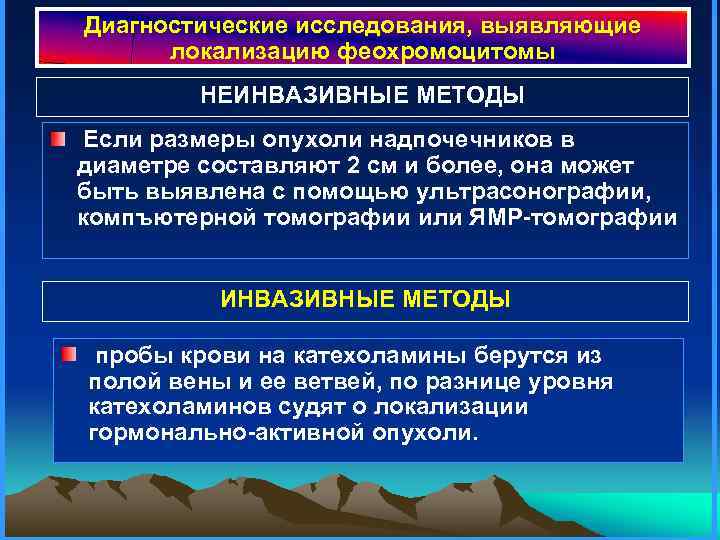

Диагностические исследования, выявляющие локализацию феохромоцитомы НЕИНВАЗИВНЫЕ МЕТОДЫ Если размеры опухоли надпочечников в диаметре составляют 2 см и более, она может быть выявлена с помощью ультрасонографии, компъютерной томографии или ЯМР-томографии ИНВАЗИВНЫЕ МЕТОДЫ пробы крови на катехоламины берутся из полой вены и ее ветвей, по разнице уровня катехоламинов судят о локализации гормонально-активной опухоли.

Диагностические исследования, выявляющие локализацию феохромоцитомы НЕИНВАЗИВНЫЕ МЕТОДЫ Если размеры опухоли надпочечников в диаметре составляют 2 см и более, она может быть выявлена с помощью ультрасонографии, компъютерной томографии или ЯМР-томографии ИНВАЗИВНЫЕ МЕТОДЫ пробы крови на катехоламины берутся из полой вены и ее ветвей, по разнице уровня катехоламинов судят о локализации гормонально-активной опухоли.